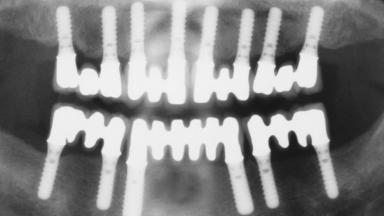

Immediate Loading of Eight Implants in the Maxilla and Six Implants in the Mandible and Final Restoration with Three-Unit and Four-Unit FDPs

Extensive scientific evidence has confirmed that immediately loaded implants with fixed full-arch provisional restorations can osseointegrate with success rates similar to conventionally or delayed loaded implants. A number of immediate-provisionalization techniques for edentulous jaws have been described. Some protocols differ when it comes to prefabricated provisional templates versus complete denture conversion; intrasurgical impressions versus direct relining; and cemented versus screw-retained provisional restorations. In this context, complete-denture conversion has been proposed for either intrasurgical impressions or direct relining. Another possibility is the utilization of a prefabricated provisional to be adapted either in the mouth (by direct relining) or in the laboratory (on a working model obtained from an intrasurgical impression).

# of Implants 14

Defining Characteristics Fully edentulous upper jaw to be rehabilitated with four or more implants

Modality 6+ implants with immediate loading